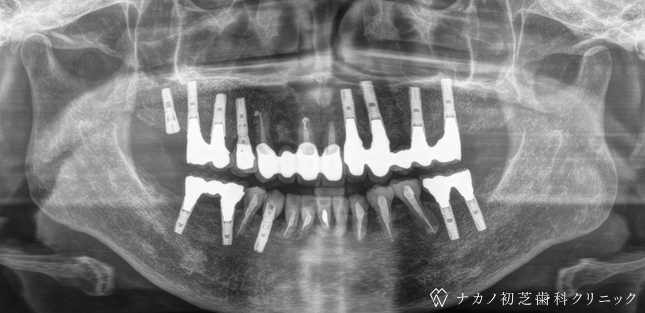

インプラント・13本 (60代女性)

BEFORE

AFTER

年齢 60代女性

治療内容 インプラント治療13本(骨造成の併用)

インプラント治療とは、歯を抜いた所にチタン製の人工歯根を埋入し、その上に歯を入れる方法です。骨を増やすことで、より審美的に治療が出来ました。費用 1本 400,000円(税込 440,000円)

リスク・副作用

腫れ・疼痛・違和感を感じるなどの症状を生じることがあります。